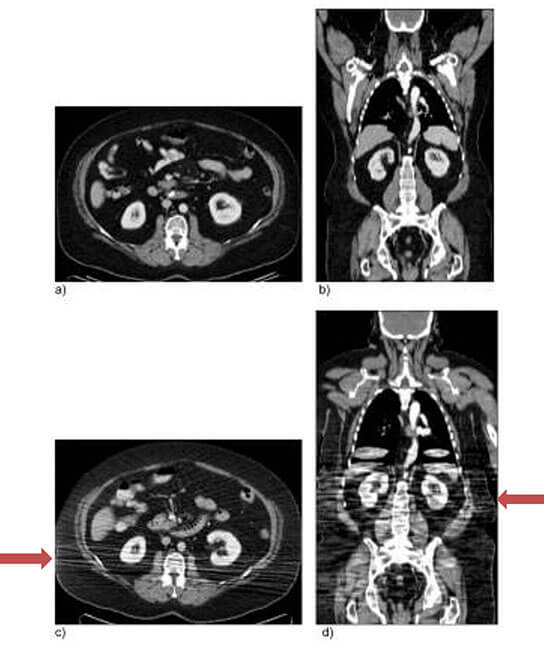

CT scanners have both weight and diameter limits. The patient, or body part of interest, must fit within the CT gantry (doughnut-shaped opening) in both the vertical and horizontal dimensions in order for the scan to occur. It is important to note that the scanner’s vertical diameter is further constrained by the table (as demonstrated by the image below) and must be taken into consideration when determining if a patient will fit into the scanner.

Images demonstrating how the table narrows gantry size, most notably in the vertical dimension.1

Axial and coronal CT images from a patient scanned positioned with their arms overhead (a,b) versus down by their side (c, d). Beam hardening artifact and decreased image quality result from the improper positioning (c, d).2